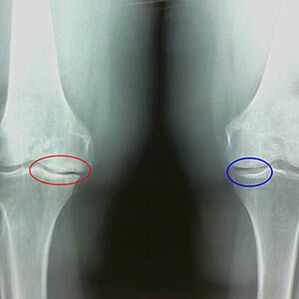

Arthroz derecesinin belirlenmesi X -Ray tarafından meydana gelirKemik yapılarının patolojik sürecine katılım. Değişikliği, kas sisteminin 5-10 yıldır dengesizlik içinde olduğunu göstermektedir. Kural olarak insanlar Birkaç yıl boyunca ağrıyan ağrılar yaşarlar.

Artrozun ilk aşamasındakazayla tespit edilen, kemik mahmuzlarında hafif bir artış meydana gelir. Büyümeler, eklemin en büyük istikrarsızlığındaki yerlerde ortaya çıkar. Tipik olarak, hastalar hareket sırasında nadiren ağrı veya rahatsızlık yaşarlar.

Artrozun ikinci aşaması kolay kabul edilir. Radyografi önemli kemik mahmuzları ortaya çıkarır, ancak kıkırdak etkilenmez. Sinovyal sıvı miktarı azalır, ancak uzun yürüme ve koşmadan sonra ağrı belirtileri, eklemde sertlik ve büküldüğünde ve dizlerin üzerindeki pozisyonda görülür.

Diz artrozunun ikinci aşamasının erken X -Ray özellikleri:

- çapraz şekilli ligamentin bağlı olduğu tibia üzerindeki inter -krip tüberküllerinin sivri kenarları;

- medial taraftaki eklem boşluğunun daralması;

- Kemiklerin kondillerinin medial kenarlardaki sivri kenarları, valgus veya varor eklem deformasyonunun gelişimine bağlı olarak daha az lateralde.

Larsen'deki ikinci aşama için Eklem boşluğunun% 50'den fazla daralması karakteristiktir, ancak bu sadece dinamik olarak kontrol edilebilir veya belirsiz bir eklemle karşılaştırılabilir.

Radyografi, osteofitlerin varlığını gösterir, femoral ve tibia kemikleri arasındaki boşlukta bir değişiklik, dizde kıkırdak kaybını gösterir. Bazen diz eklemlerinin X ışını önemli kıkırdak aşınma belirtileri gösterir, ancak hastalar önemli ağrı yaşamaz.Aksine, ilk aşamanın eklemozu dizinin işlevini bozabilirağrı nedeni hipotonik kaslardır.